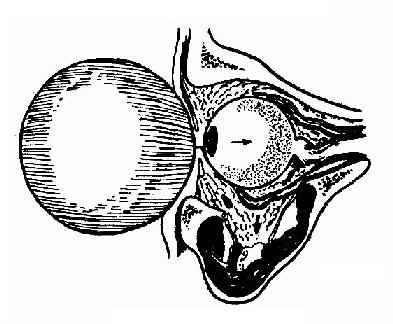

(三)眶底爆折:眼眶前方受钝器击伤时,眶内压骤增致使眶底壁骨折,称眶底爆折。眶底骨折片和眶骨摸、脂肪、下直肌、下斜肌等组织陷入上颌窦内,出现眼球塌陷、上下运动障碍及复视。如伴有眼球和视神经损伤则视力减退或失明。(图13-6)。

图13-6 眶底爆折